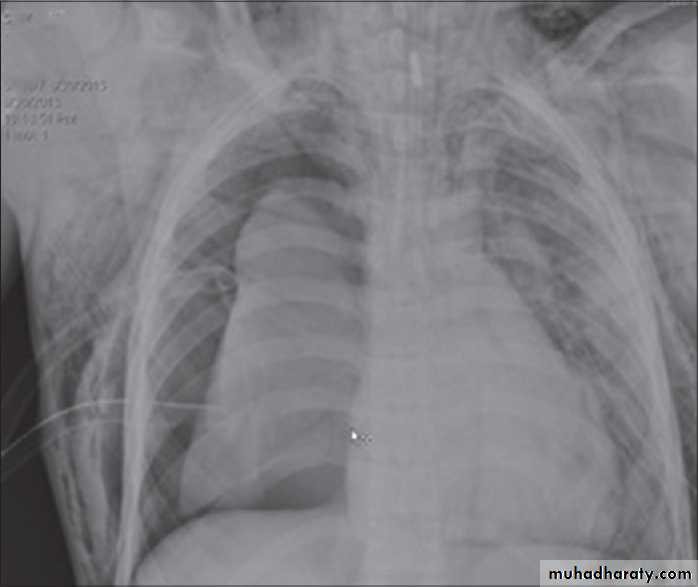

Foreign body in right bronchus

Foreign body in bronchus

Abdominal surgery before 2 days

Fall from the 2nd floor